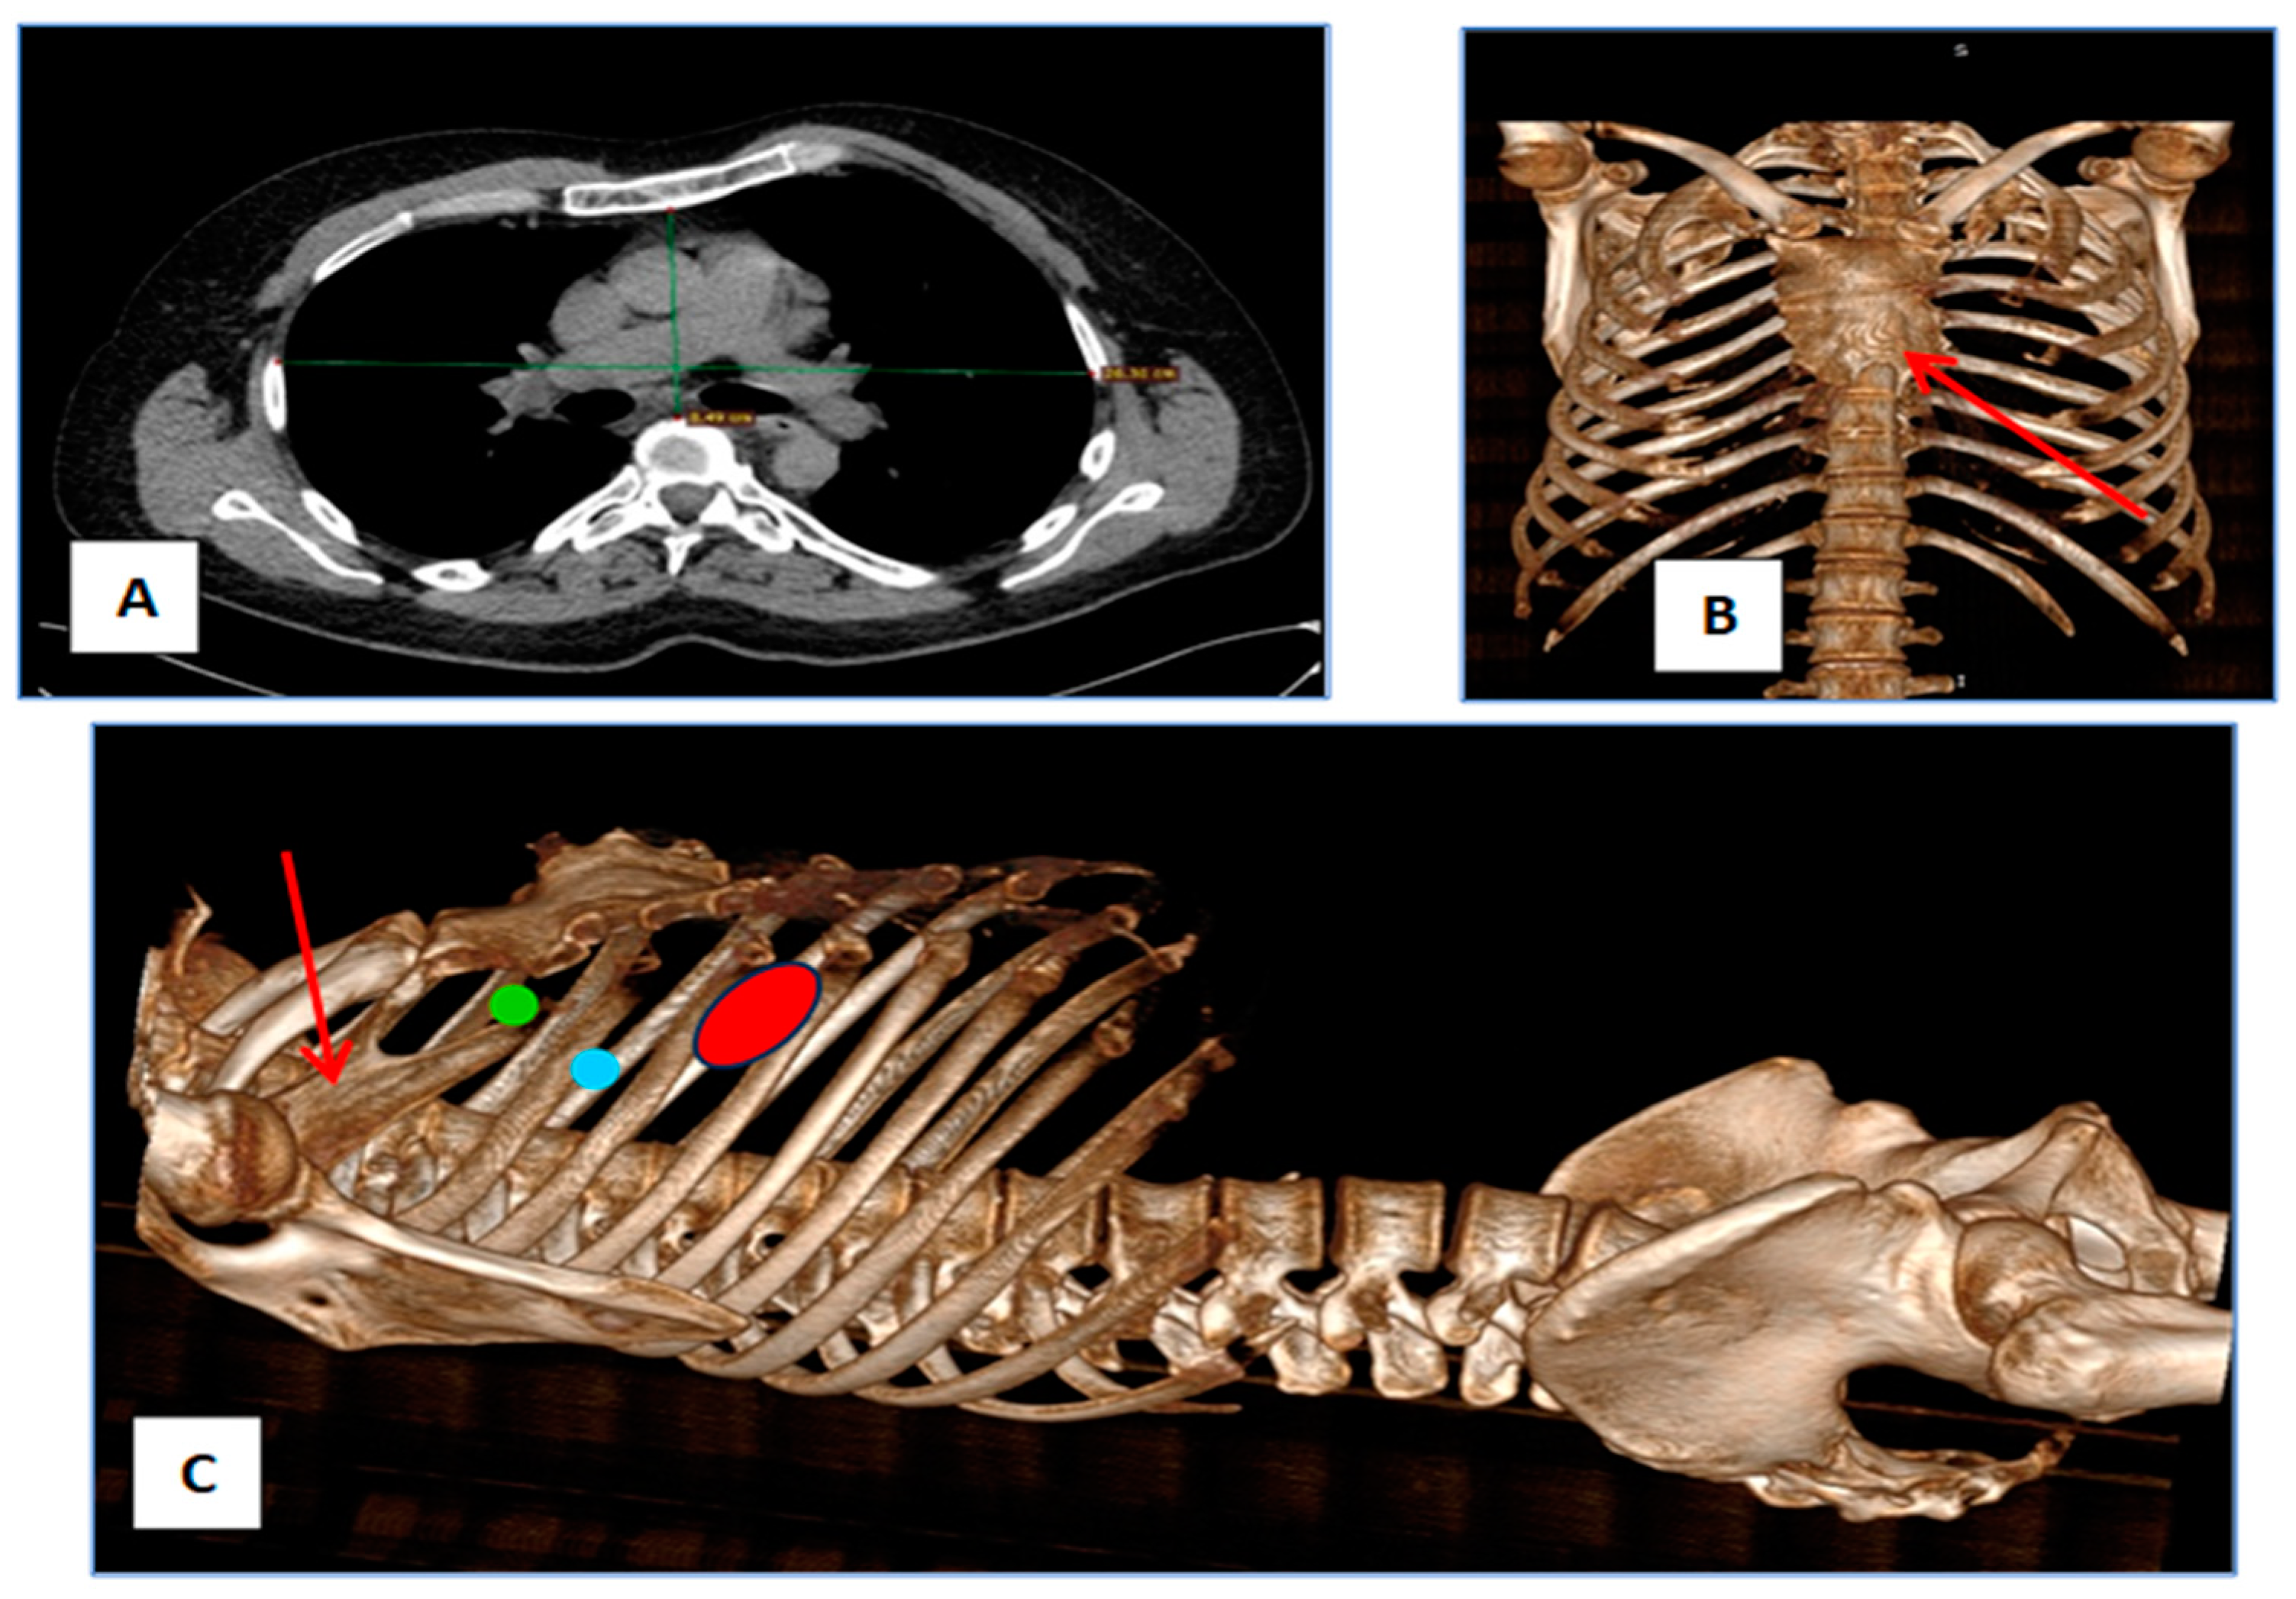

2. Case Report